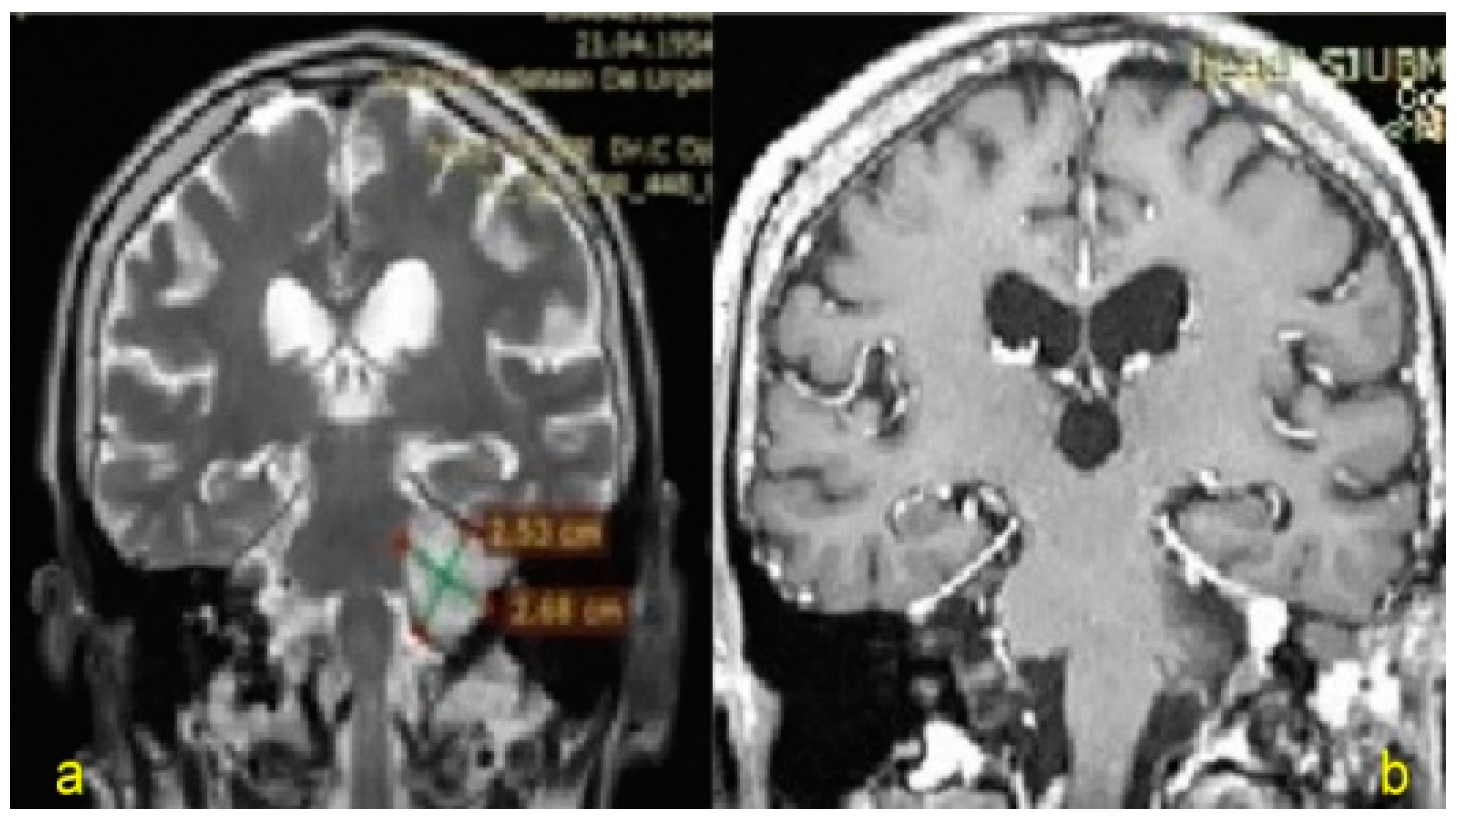

| 1. | 61/F | VS (Jun 2015) Koos grade IV(large tumor with brainstem displacement) | Breast cancer(treated surgically in 2013), CIPN—TNSc grade 2 | 19 | Tarsorrhaphy | VI/III (right side) Total paralysis/obvious weakness but not totally disfiguring, complete eye closure with effort and symmetric at rest | - |

| 2. | 65/F | VS (Sep 2016) Koos grade IV | Uterine cancer, Melanoma (treated surgically in 2014), CIPN—TNSc grade 2 | 13 | Tarsorrhaphy | VI/III (right side) | - |

| 3. | 64/M | VS (Apr 2015) Koos grade IV | - | 26 | Tarsorrhaphy | VI/IV (left side) Total paralysis/Disfiguring weakness, incomplete eye closure and asymmetric at rest | CSF leak Hydrocephalus (VCS, right VP shunt) |

| 4. | 63/F | VS (Jan 2018) Koos grade IV | Chronic hypothyroidism (2006) PN—TNSc grade 2 | 6 | Tarsorrhaphy | VI/IV (left side) | - |